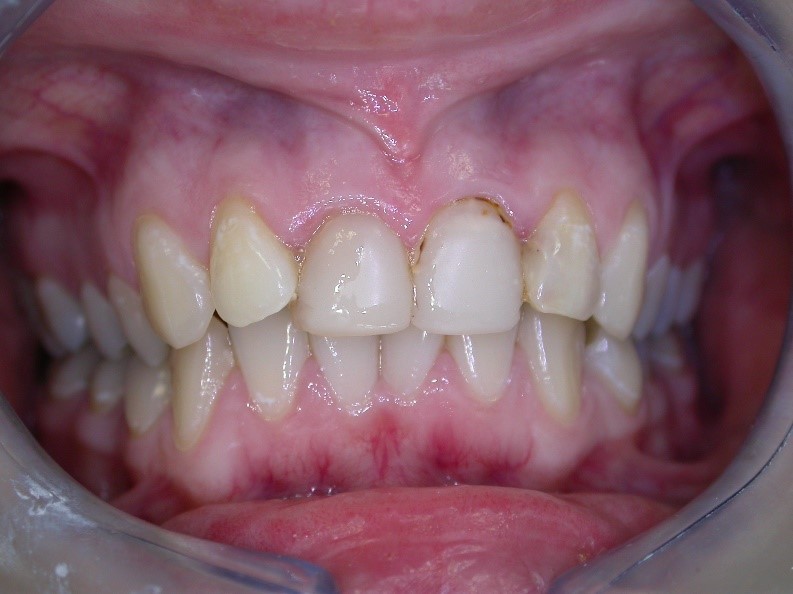

Úprava estetiky chrupu pomocí laboratorně zhotovených keramických korunek.

Korunky zhotovujeme u velkého poškození zubu nebo z estetických důvodů. Nejčastěji používáme celokeramické korunky a metalokeramické korunky. Ošetření probíhá ve dvou návštěvách, v první návštěvě je nutné zub nabrousit a udělat otisk, který posíláme do laboratoře. Z ordinace odcházíte s dočasnou korunkou, která brání pohybu sousedních zubů a mechanicky chrání připravený zub. Po 10ti dnech, tedy času, který potřebuje laboratoř, Vám po sejmutí provizoria, odevzdáme Vaše nové korunky.

Ukázky naší práce